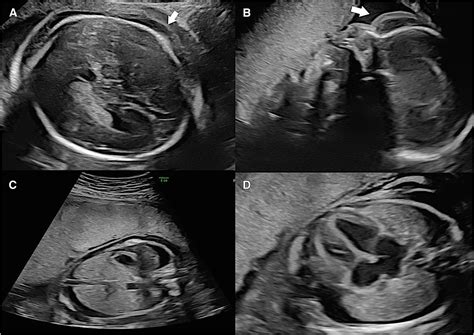

• Abnormal Ultrasound Findings: Ultrasound examinations may reveal fluid accumulation in the fetal tissues or body cavities.

• Ultrasound: Ultrasound examinations are the most common method for detecting fetal edema. They can reveal fluid accumulation in the fetal tissues and body cavities.